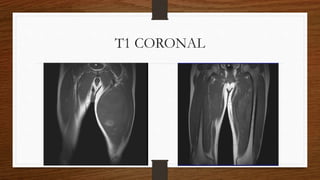

SecuenciasT1 CORONAL

T1 CORONAL

SecuenciasT1 CORONAL T2 STIRCORONAL T2 TSE CORONAL T2 STIR SAGITAL T1 TSE AXIAL